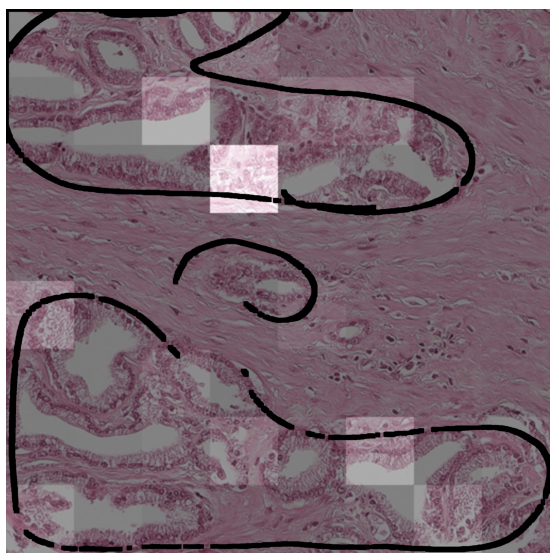

In a first analysis we use the Gleason dataset to create an artificial dataset for which the annotation per image patch is known. Each image in this dataset combines one image showing benign tissue and one image with malignant Gleason grade 5 tissue by stitching half of each together (see example in \figurereffig:fake_attention_example_img). For each image, the attention weights per patch are extracted from the MIL layer of eCaReNet. In the example it can be seen that the upper, malignant part, receives the highest attention weights, while in the benign tissue only relatively bright regions are highlighted. This may be because white regions correspond to glands, which are an important structure to distinguish benign from malignant tissue (see also \figurereffig:apd_att). A boxplot of the attention weights of all 12 example images is shown in \figurereffig:fake_attention_example_box. The attention weights for malignant patches are significantly higher than for benign patches. The original images that were stitched together are neither part of the training nor of the validation or test sets and give an unbiased estimate of importance.

Another experiment was conducted on the survival dataset. From each TMA, one image was randomly chosen from both the validation and test sets of the survival dataset, while maintaining the overall data distribution with respect to the ISUP grades, relapse time and censoring status. An expert pathologist marked tumor regions in each image, enabling us to compare this to the attention weights per patch. A patch is counted as tumorous if 66% of it lie within the marked tumor region. \figurereffig:annotation_example_img shows that all highlighted patches lie within the tumor area, however not all patches in the tumor area receive a high attention weight. \figurereffig:annotation_example_box shows the results on all images showing tumor tissue drawn from the test set. Patches marked as tumor show on average higher attention weights than non-tumor image patches.

As an additional example for the experiment described in \sectionrefsec:attention, \figurereffig:apd_att is provided. Also here it is shown that the malignant patches (in the lower part of the image) receive higher attention weights.